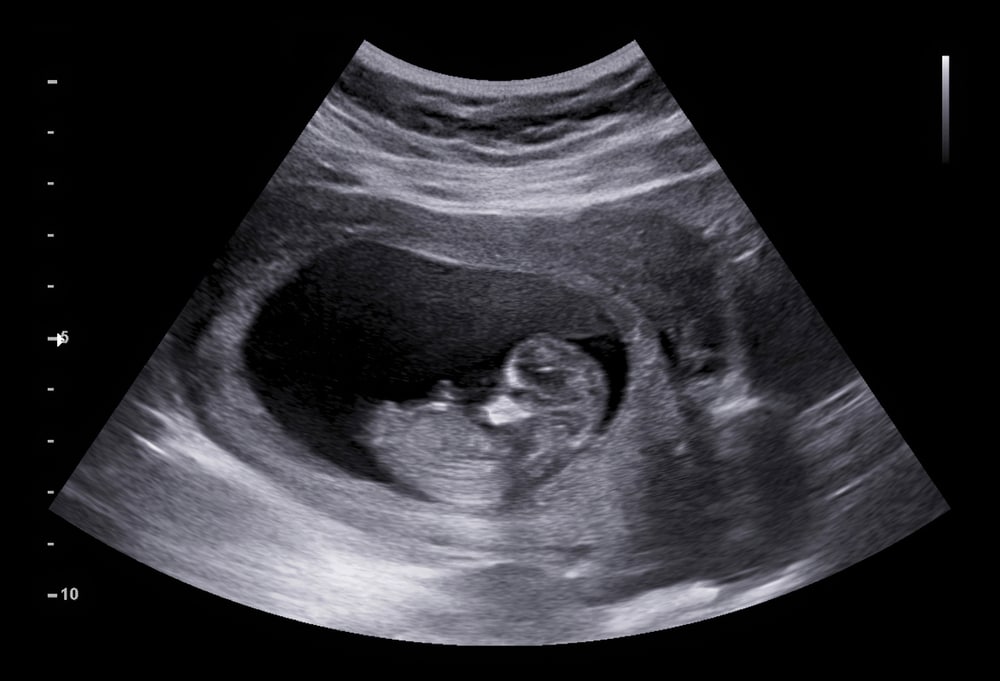

नैनीताल। जिले के बीडी पांडे अस्पताल में मंगलवार को एक चौंकाने वाला मामला सामने आया, जिससे हड़कंप मच गया। पेट दर्द की शिकायत लेकर उपचार के लिए पहुंची 16 वर्षीय एक नाबालिग किशोरी की अल्ट्रासाउंड जांच में उसके एक माह की गर्भवती होने की जानकारी मिली। यह खबर सुनते ही किशोरी की मां और परिवार के अन्य सदस्य पूरी तरह से स्तब्ध रह गए।

मंगलवार को क्षेत्र की यह नाबालिग अपनी मां के साथ पेट दर्द की शिकायत लेकर अस्पताल पहुंची थी। डॉक्टरों ने जब जांच की, तो उन्हें किशोरी के गर्भवती होने का पता चला। मामले की गंभीरता को देखते हुए, अस्पताल प्रबंधन ने तत्काल नैनीताल पुलिस को इसकी सूचना दी। सूचना मिलते ही कोतवाली पुलिस मौके पर पहुंची और किशोरी व उसकी मां से इस संबंध में गहनता से पूछताछ की।